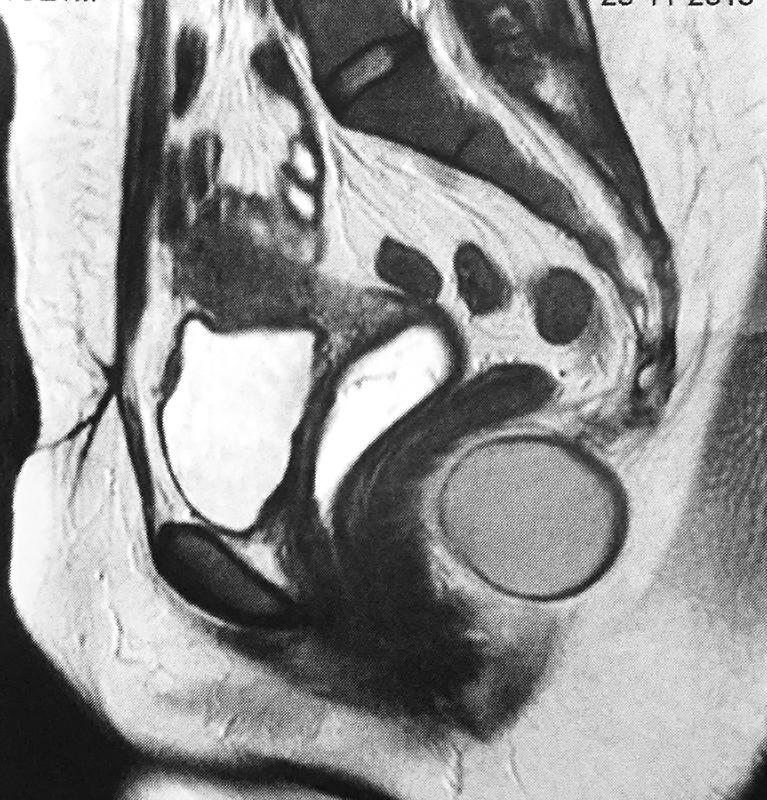

Tumor Cístico retrorretal

Retrorectal cystic tumors

Caso Código 223A de Tumor Cístico retrorretal - Case Code 223A of Retrorectal cystic tumors

RNM evidenciando tumoração cística retrorretal, deslocando reto anteriormente.